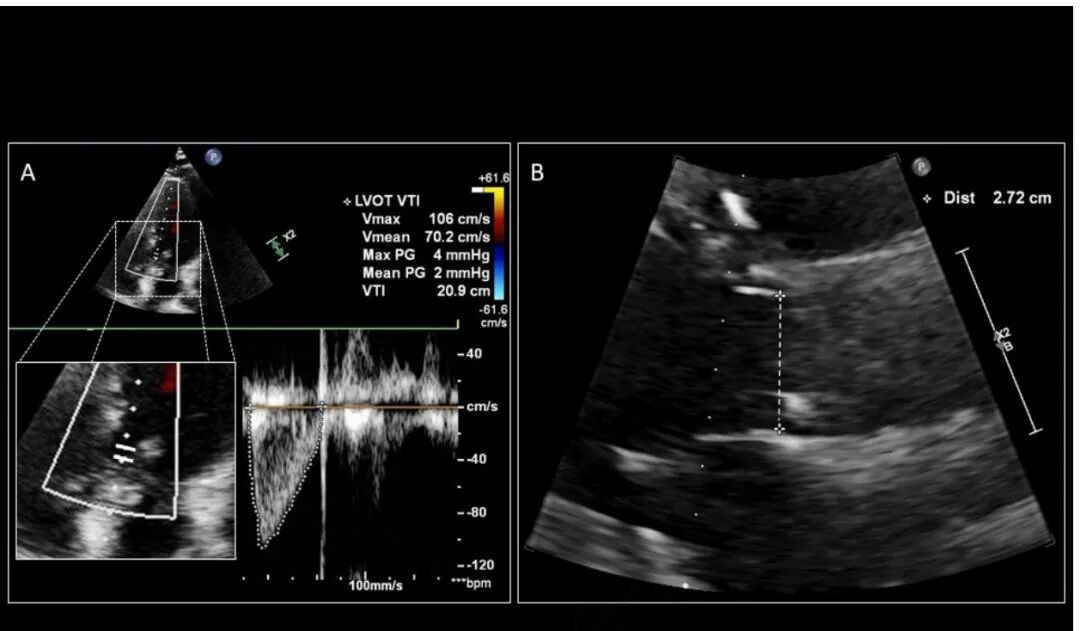

4. 脉冲波 (PW) 多普勒用于利用小样本量获得接近 AV 的 VTI,并优化 VTI 包络以进行跟踪(图 2A)。

7. 放大并测量 LVOT 直径,从收缩早期到中期的内缘到内缘,就在 AV 近端(图 2B)。

图 2. 使用 (A) A5c 视图中从 LVOT 近端到主动脉瓣的 PW 多普勒样本的 VTI 跟踪,和 (B) 测量 LVOT 直径的 PLAX 来评估每搏量

图 4. 比较多普勒采样线 (A) 与血流平行与 (B) 离轴大于 20˚ 时产生的 LVOT VTI 差异。